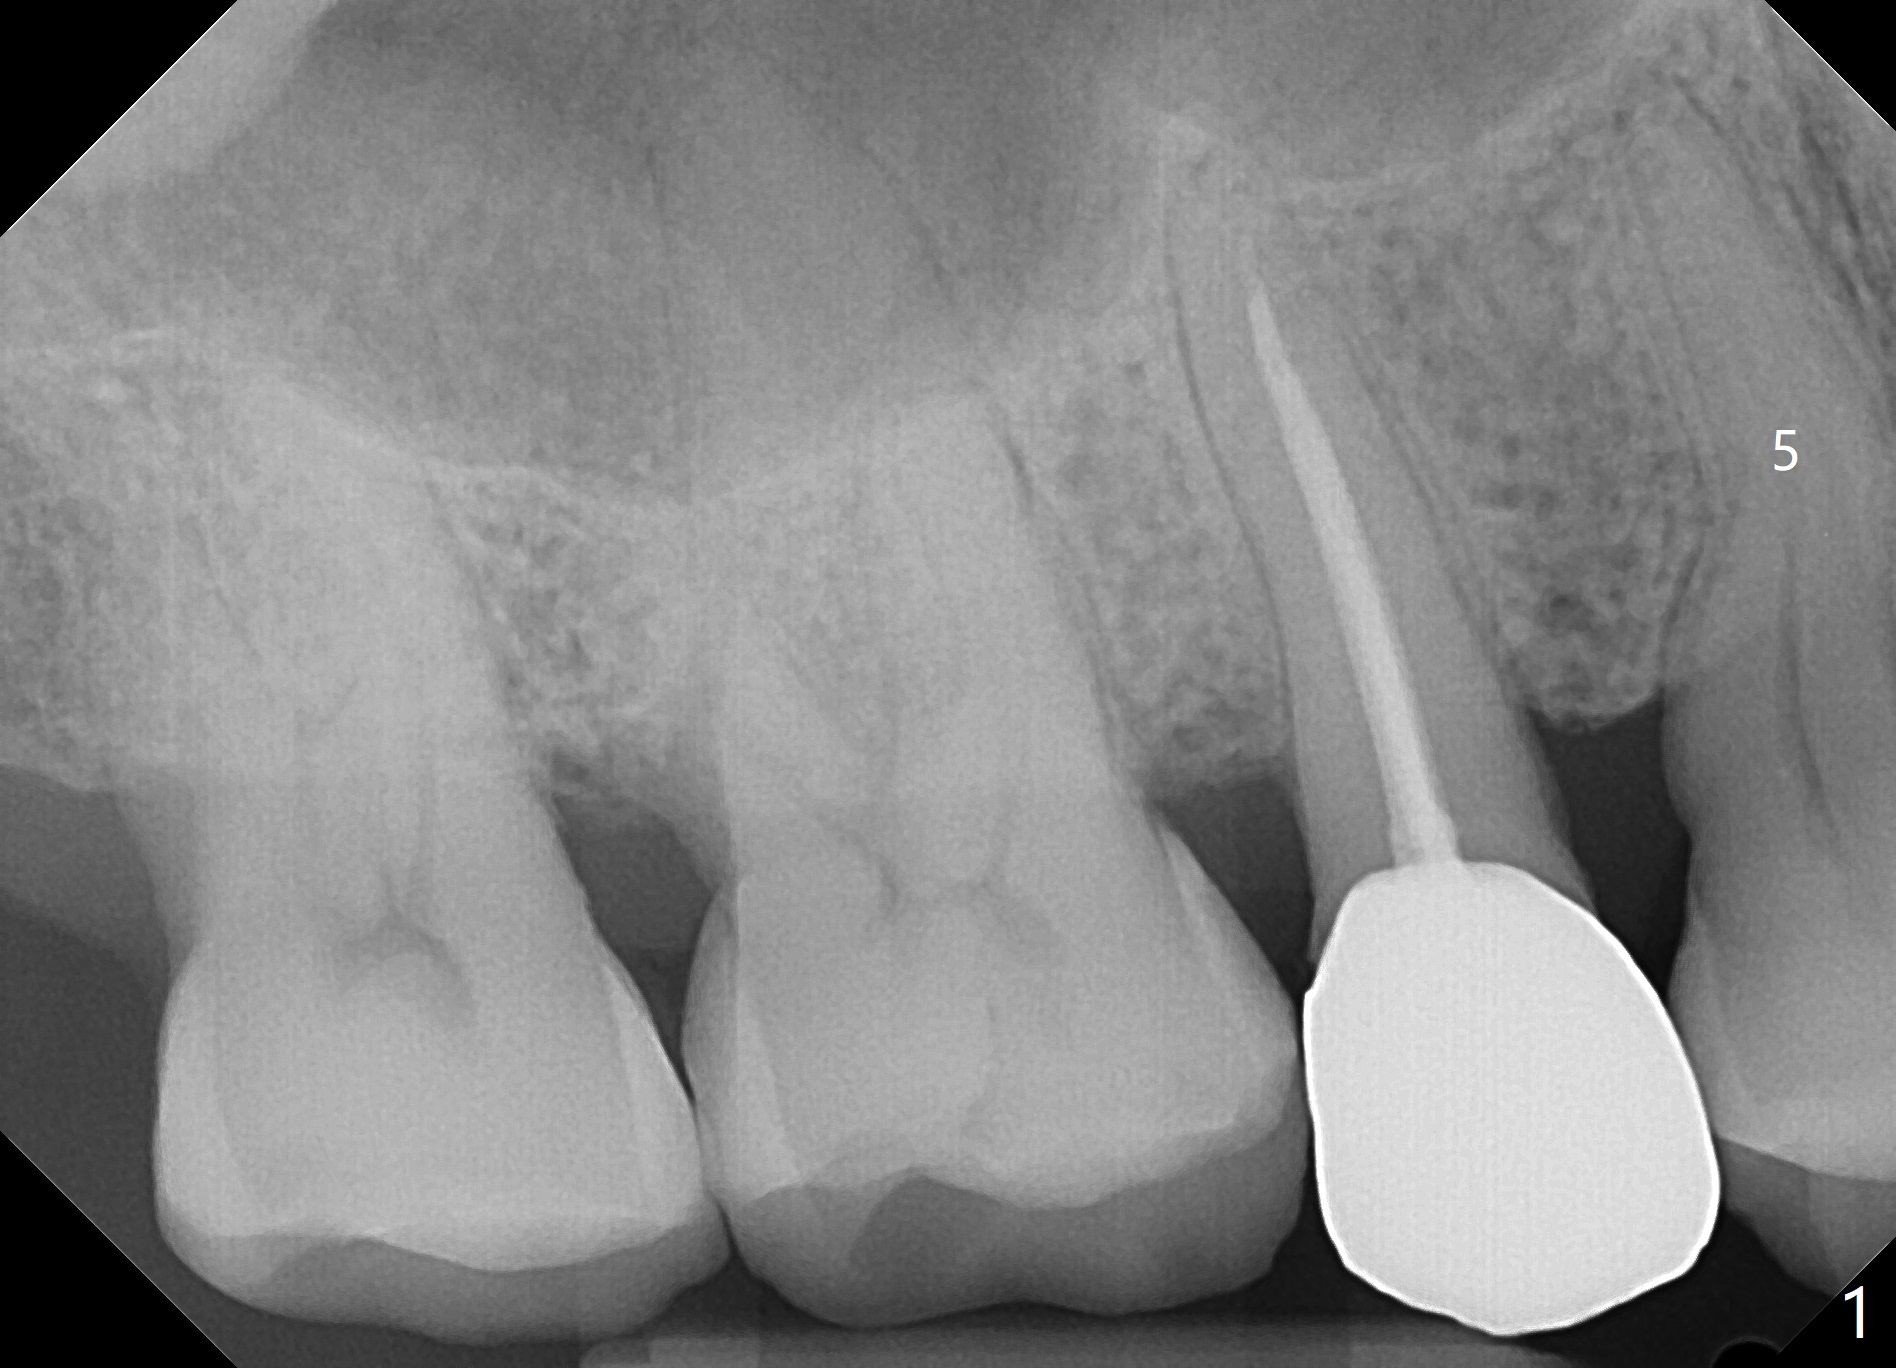

A 63-year-old man develops cold and hot sensitivity in the upper right 1st premolar after crack noise. The tooth #5 has a mesiodistal crack line (Fig.1-2). Two weeks later, the palatal cusp fractures subgingival. There is no time for guide (Fig.3). Since the root is curved and apparently difficult to extract, prepare surgical hand piece for socket shield.